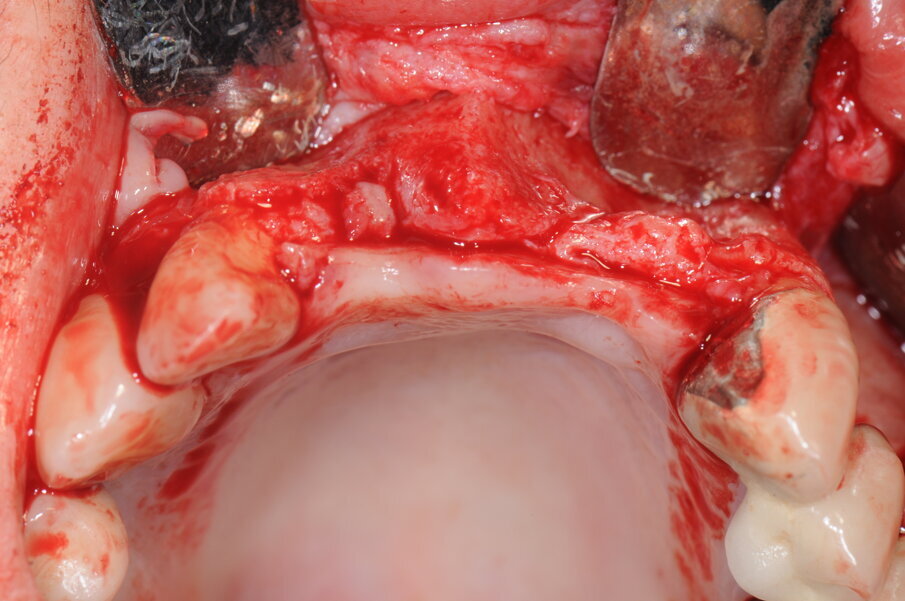

Dopo le procedure di anestesia locale (Articaina 4% con adrenalina 1:100.000), è stata eseguita un’incisione intrasulculare che interessava gli elementi 1.2, 1.3, 1.4 per proseguirsi con un’incisione crestale e intrasulculare degli elementi 2.3, 2.4 dal quale è stata eseguita l’incisione di scarico. Il lembo è stato scollato a spessore totale e successivamente passivato per mezzo di un’incisione periostale di rilascio. La superficie ossea esposta, presentava un più marcato riassorbimento osseo in senso orizzontale rispetto a quello verticale.

Figg. 8a, 8b - Esposizione del sito chirurgico e valutazione dei volumi ossei.